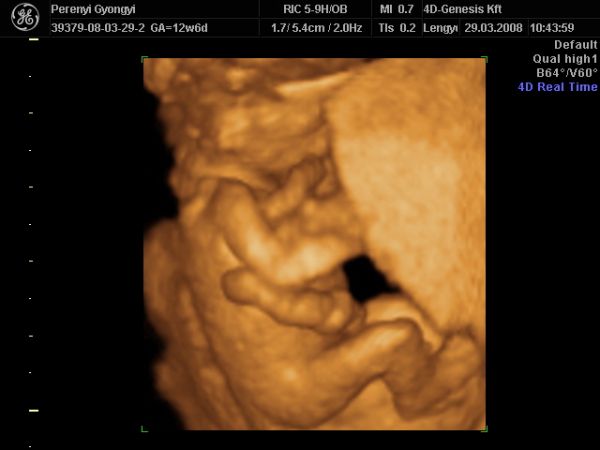

NHS-ben (TB kb), ami ingyen van 2db Uh van...12 és 20 hetesen. Ezen kívül minden hónapban találka a midwife-al, aki vizeletet néz, vérnyomást mér, megkérdezi hogy vagy, és elbeszélget veled, ha kérdésed, problémád, félelmed van. Aztán vannak a magán kórházak, ahova a középosztály felettiek járnak. Itt ugye annyit mehetsz, amennyit bír a pénztárcád, de mivel itt az előbbi a bevett szokás, sok nő nem kér semmi extrát. A privát ellátásért és szülésért viszont a végén kb egy 500-600 fontos számlát kapsz. Akire vigyázok, ő is ennyiért született. De ők nem kértek semmi extrát, 4D-re sem mentek el. Ja és aki NHS-re jár, de nem bír magával, az elmehet UH studiokba, amik a 4D-re mennek rá, de van 2D-s korai Uh is...mint pl majd én is leszek nagy valószínűség szerint.